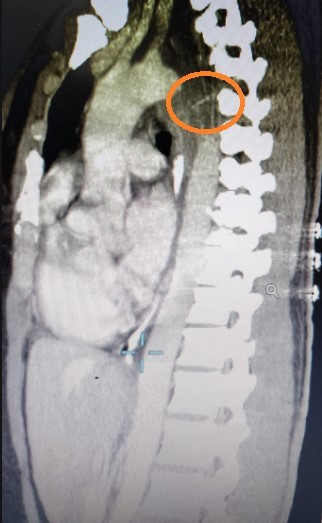

Hình ảnh CT scaner ngực phát hiện xương cá được khoanh tròn đỏHình ảnh CT scaner ngực phát hiện xương cá được khoanh tròn đỏ

Ngày sau bệnh nhân nội soi đánh giá tiến triển phát hiện có dịch mủ màu trắng sữa chảy ra từ phía ngoài thực quản chảy vào lòng thực quản. Sau đó xem đánh giá trên CT scaner ngực thấy thành thực quản dày chạy dọc phù nề thâm nhiễm có ít dịch cạnh thực quản, có dị vật nghi xương trong khoang trung thất cạnh thực quản. Hỏi tiền sử bệnh nhân có ăn thức ăn là canh cá trước đó 8 ngày.